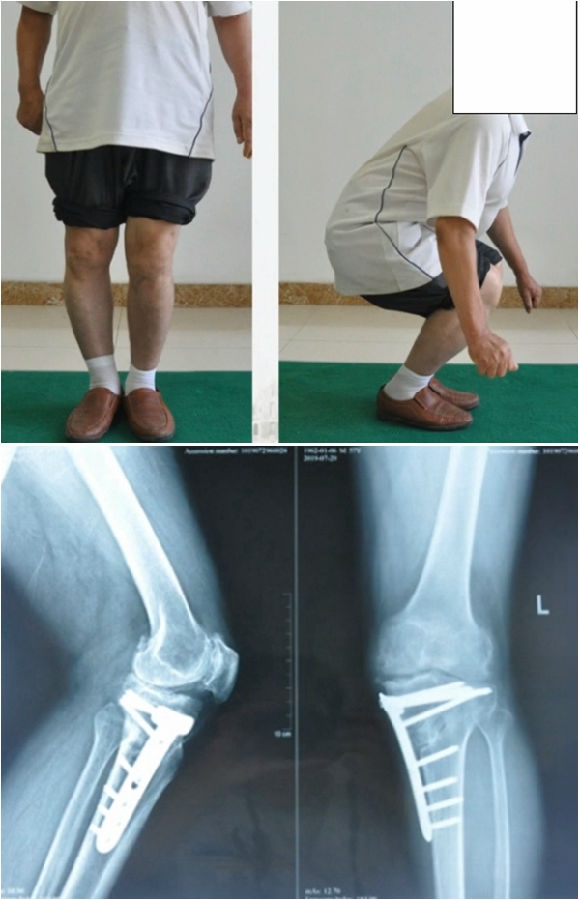

典型病例,男性,65岁,农民,双膝内翻16度。

术前影像

第一次为该患者做了传统上行开放截骨,撑开角度较大,术后用三种方法测量髌骨高度,发现髌骨高度受到影响,髌骨变低了。

左膝上行OWHTO(初次)

上行OWHTO髌骨高度测量

ISI法测量髌骨无明显变化;CDI、BPI法测量髌骨降低明显;患者屈膝锻炼困难。

第二次来院做另一侧肢体时,采用下行截骨,术后患者髌骨高度,无论用哪种方法测量都无明显变化,而且患者膝关节功能迅速得到恢复。

右膝下行OWHTO(再次)

下行OWHTO髌骨高度测量

ISI法测量髌骨无明显变化;CDI、BPI法测量髌骨无明显变化;患者屈膝明显改善。